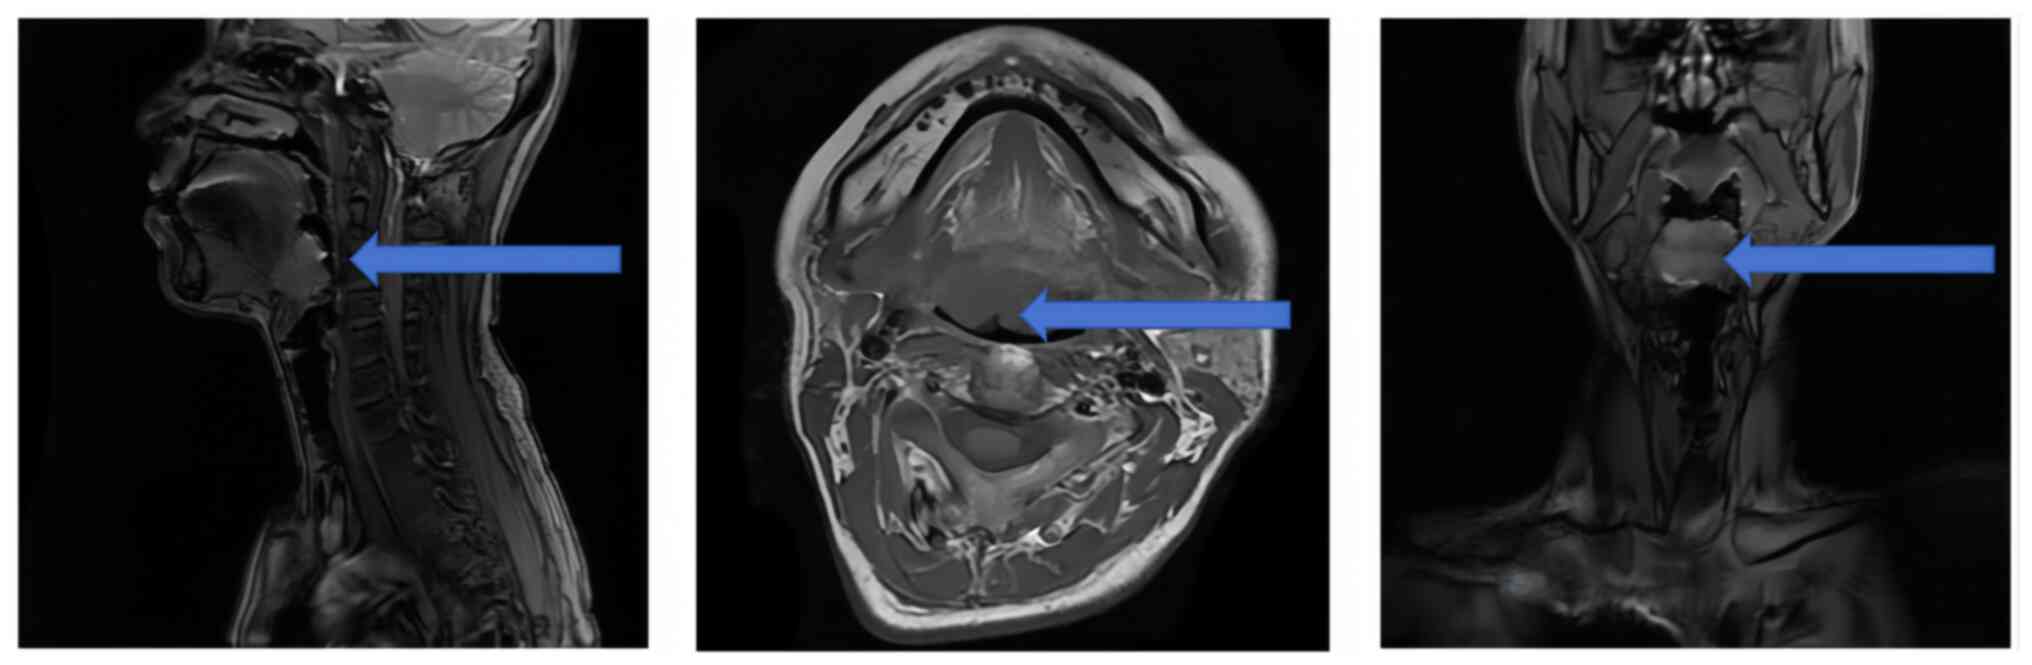

A rare case of hyalinizing clear cell carcinoma of the tongue root: A case report and literature review

The present study describes a rare case of hyalinizing clear cell carcinoma (HCCC) of the tongue root and provides an analysis and review of the relevant literature to improve the understanding of its diagnosis and treatment. Clinical imaging and pathological data from a patient with primary HCCC of the tongue root were summarized, and previously published studies were reviewed through a literature search. The common symptoms, treatment strategies and prognoses reported in the literature were compared. A total of 16 cases of primary HCCC of the tongue were retrieved. Histologically, these cases had tumors characterized by clear cells arranged in sheets, nests and cords within the fibrous interstitium surrounding tumor cells, with round to oval cell nuclei occasionally containing small or inconspicuous nucleoli. Immunohistochemistry showed positive tumor cell staining for cytokeratin (CK)5/6, CK7 and p63, and negative for S‑100, smooth muscle actin and calponin. Clinical symptoms included dysphagia, a painless mass, tongue root ulceration and a foreign body sensation in the throat. Treatment strategies included surgery, radiation therapy, repair and reconstruction, with no local recurrence or metastasis at any follow‑up point. The present findings indicated that HCCC of the salivary glands is an inert malignant tumor, and a good prognosis can be achieved with both surgical resection and radiation therapy.

Figure 1